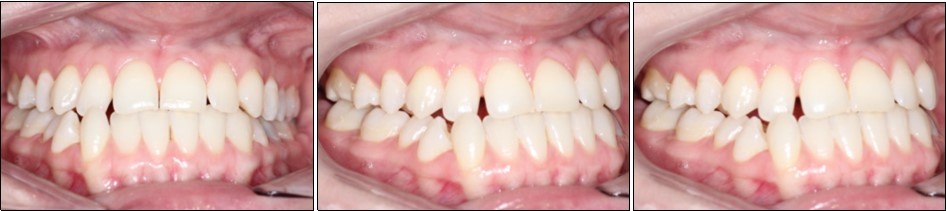

Intraoral examination revealed bilateral Angle’s class III molar relationship, class III canine relationship on the right and class I on the left, a deviated lower dental midline to the left of the patient, a visible negative tip in the right upper lateral incisor and canine, crossbite between 1.2. and 4.3 and 4.4, retroclined lower incisors, proclined upper incisors, with a 1 mm overbite and overjet . (Figure 2)

Figure 2.Initial intraoral photographs

Initial intraoral photographs